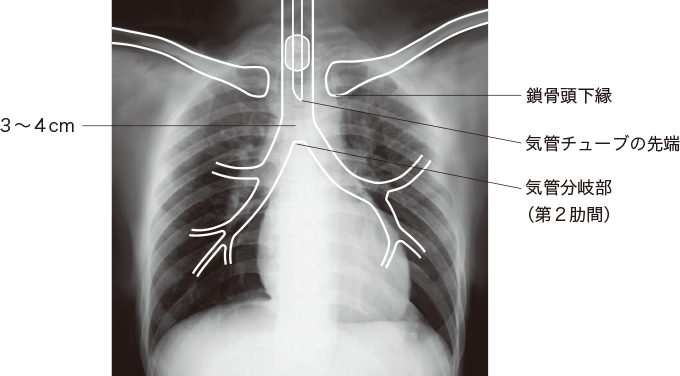

気管チューブの位置を把握するため胸部X線撮影を行い、適切な位置にあるか(気管分岐部より3~4cm上)確認します(図4)。

気管チューブの位置のずれがある場合は、位置調整を行います。

図4胸部X線